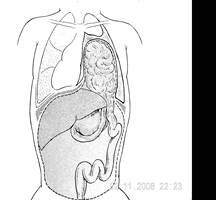

Рис.13. Истинная врожденная диафрагмальная грыжа.

Рис. 14. Ложная врожденная диафрагмальная грыжа